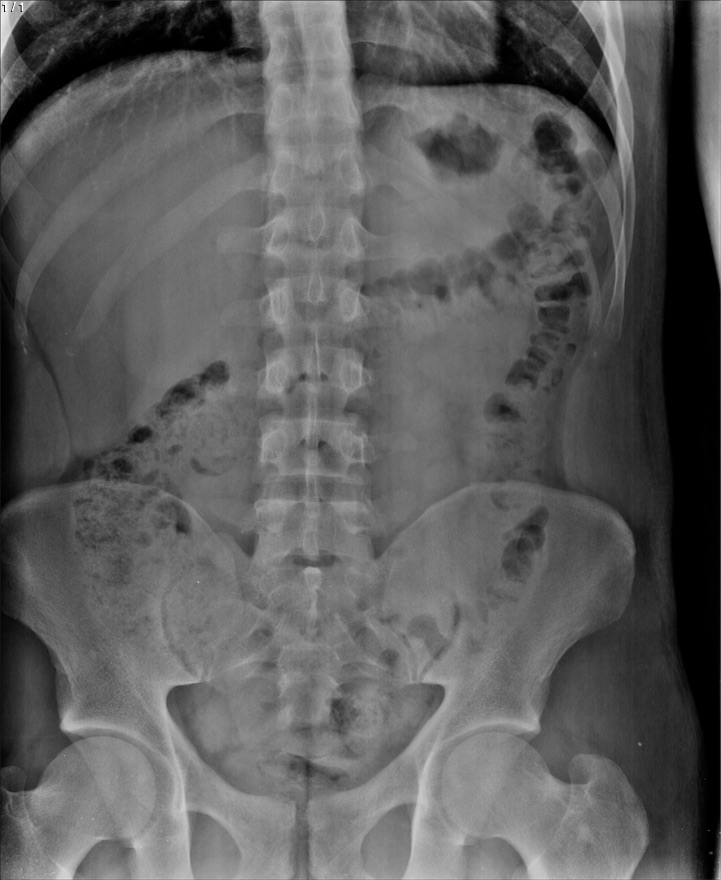

Jesus Cardenaz De Leon - Unnamed